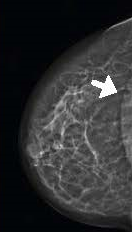

Planmed Clarity™3D – цифровая система для маммографии с томосинтезом. Метод томосинтеза позволяет более четко визуализировать уплотнения и аномальные изменения молочных желёз, что увеличивает шанс на выявление рака груди на ранних стадиях.

- ContinuousSync -and-Shoot™ - синхронизированная съёмка для непрерывной визуализации, которая позволяет получать чёткие снимки без расплывчатых границ. Синхронизацию обеспечивает детектор, который всегда сфокусирован на фокальном пятне, в то время как топографическая трубка движется по заданным параметрам. Такая технология позволяет увидеть мельчайшие детали тонких тканей и микроскопических кальцификаций.

- TomoMarker™ - это чёткие снимки без артефактов с увеличенной резкостью. Специалист видит больше, чем ранее было возможно, за счёт оптимальной геометрии съёмки под углами +/- 15°. Технология проводит итоговую итеративную реконструкцию, предоставляя качественную и чёткую картинку.